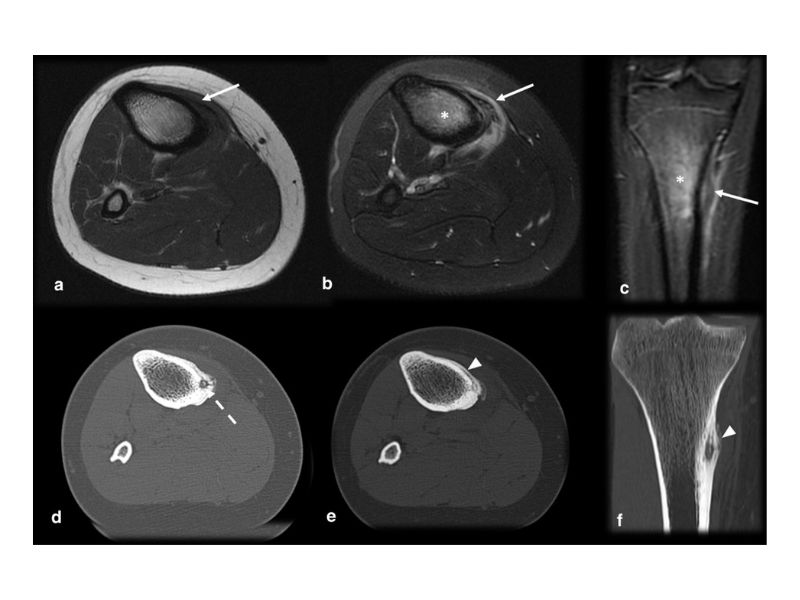

Chẩn đoán u xương dạng xương đòi hỏi sự kết hợp giữa thăm khám lâm sàng và các phương pháp chẩn đoán hình ảnh hiện đại. Trong đó, chụp X-quang thường là phương pháp đầu tiên được chỉ định nhằm phát hiện tổn thương điển hình của u xương dạng xương. Hình ảnh X-quang cho thấy một khối tổn thương nhỏ, tròn, có vùng trung tâm sáng (nidus) không cản quang với xơ cứng xung quanh. Tuy nhiên, độ nhạy của X-quang khá thấp, dẫn đến khó phát hiện sớm căn bệnh này.

- Chụp cắt lớp vi tính (CT scan) là công cụ quan trọng trong chẩn đoán chính xác vị trí khối u, đặc biệt trong các trường hợp tổn thương nằm ở cột sống hoặc khớp háng. CT cho phép xác định ổ nidus với hình ảnh đặc trưng là vùng xơ cứng bao quanh tổn thương hình bia, giúp phân biệt với các bệnh lý xương khác. Chụp CT có cản quang còn cung cấp thêm thông tin về tưới máu của khối u, hỗ trợ đánh giá mức độ lan rộng.

- Chụp cộng hưởng từ (MRI) được sử dụng để đánh giá tổn thương mô mềm liên quan, nhưng hiệu quả trong việc xác định nidus không cao bằng CT. MRI thường được chỉ định khi có nghi ngờ tổn thương xương phức tạp hoặc cần loại trừ các bệnh lý khác.

- Chụp xạ hình xương (bone scan) là phương pháp có độ nhạy cao, có thể xác định nidus nhỏ hơn 2mm và đặc trưng bởi hình ảnh "dấu hiệu mật độ kép" – vùng hấp thụ mạnh ở trung tâm và vùng hấp thụ kém ở ngoại vi.